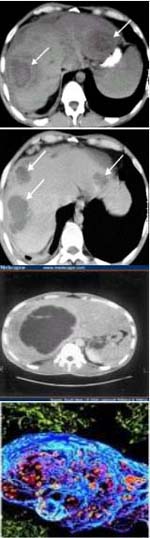

CT Scanner: trong giai đoạn sớm, ổ áp-xe cho hình ảnh của một khối có đậm độ hơi giảm hơn so với đậm độ của mô gan chung quanh, khối này có giới hạn không rõ. Khi bơm thuốc cản quang, khối sẽ hiện hình rõ hơn, do nhu mô gan chung quanh tăng quang, làm tăng sự tương phản về đậm độ cản quang giữa khối và nhu mô gan. Có thể có hiện tượng tăng quang ở phần ngoại vi của khối. Khi ổ áp-xe đã hoá lỏng hoại tử hoàn toàn, trên CT Scanner cho thấy ổ áp-xe là khối giảm đậm độ, giới hạn rõ và không tăng quang khi bơm thuốc.

Công cụ CT Scanner có độ nhạy trong chẩn đoán cao hơn so với siêu âm (95-100%), đồng thời CT cũng có thể phát hiện các tổn thương khác tại các cơ quan lân cận và vùng gan mật.